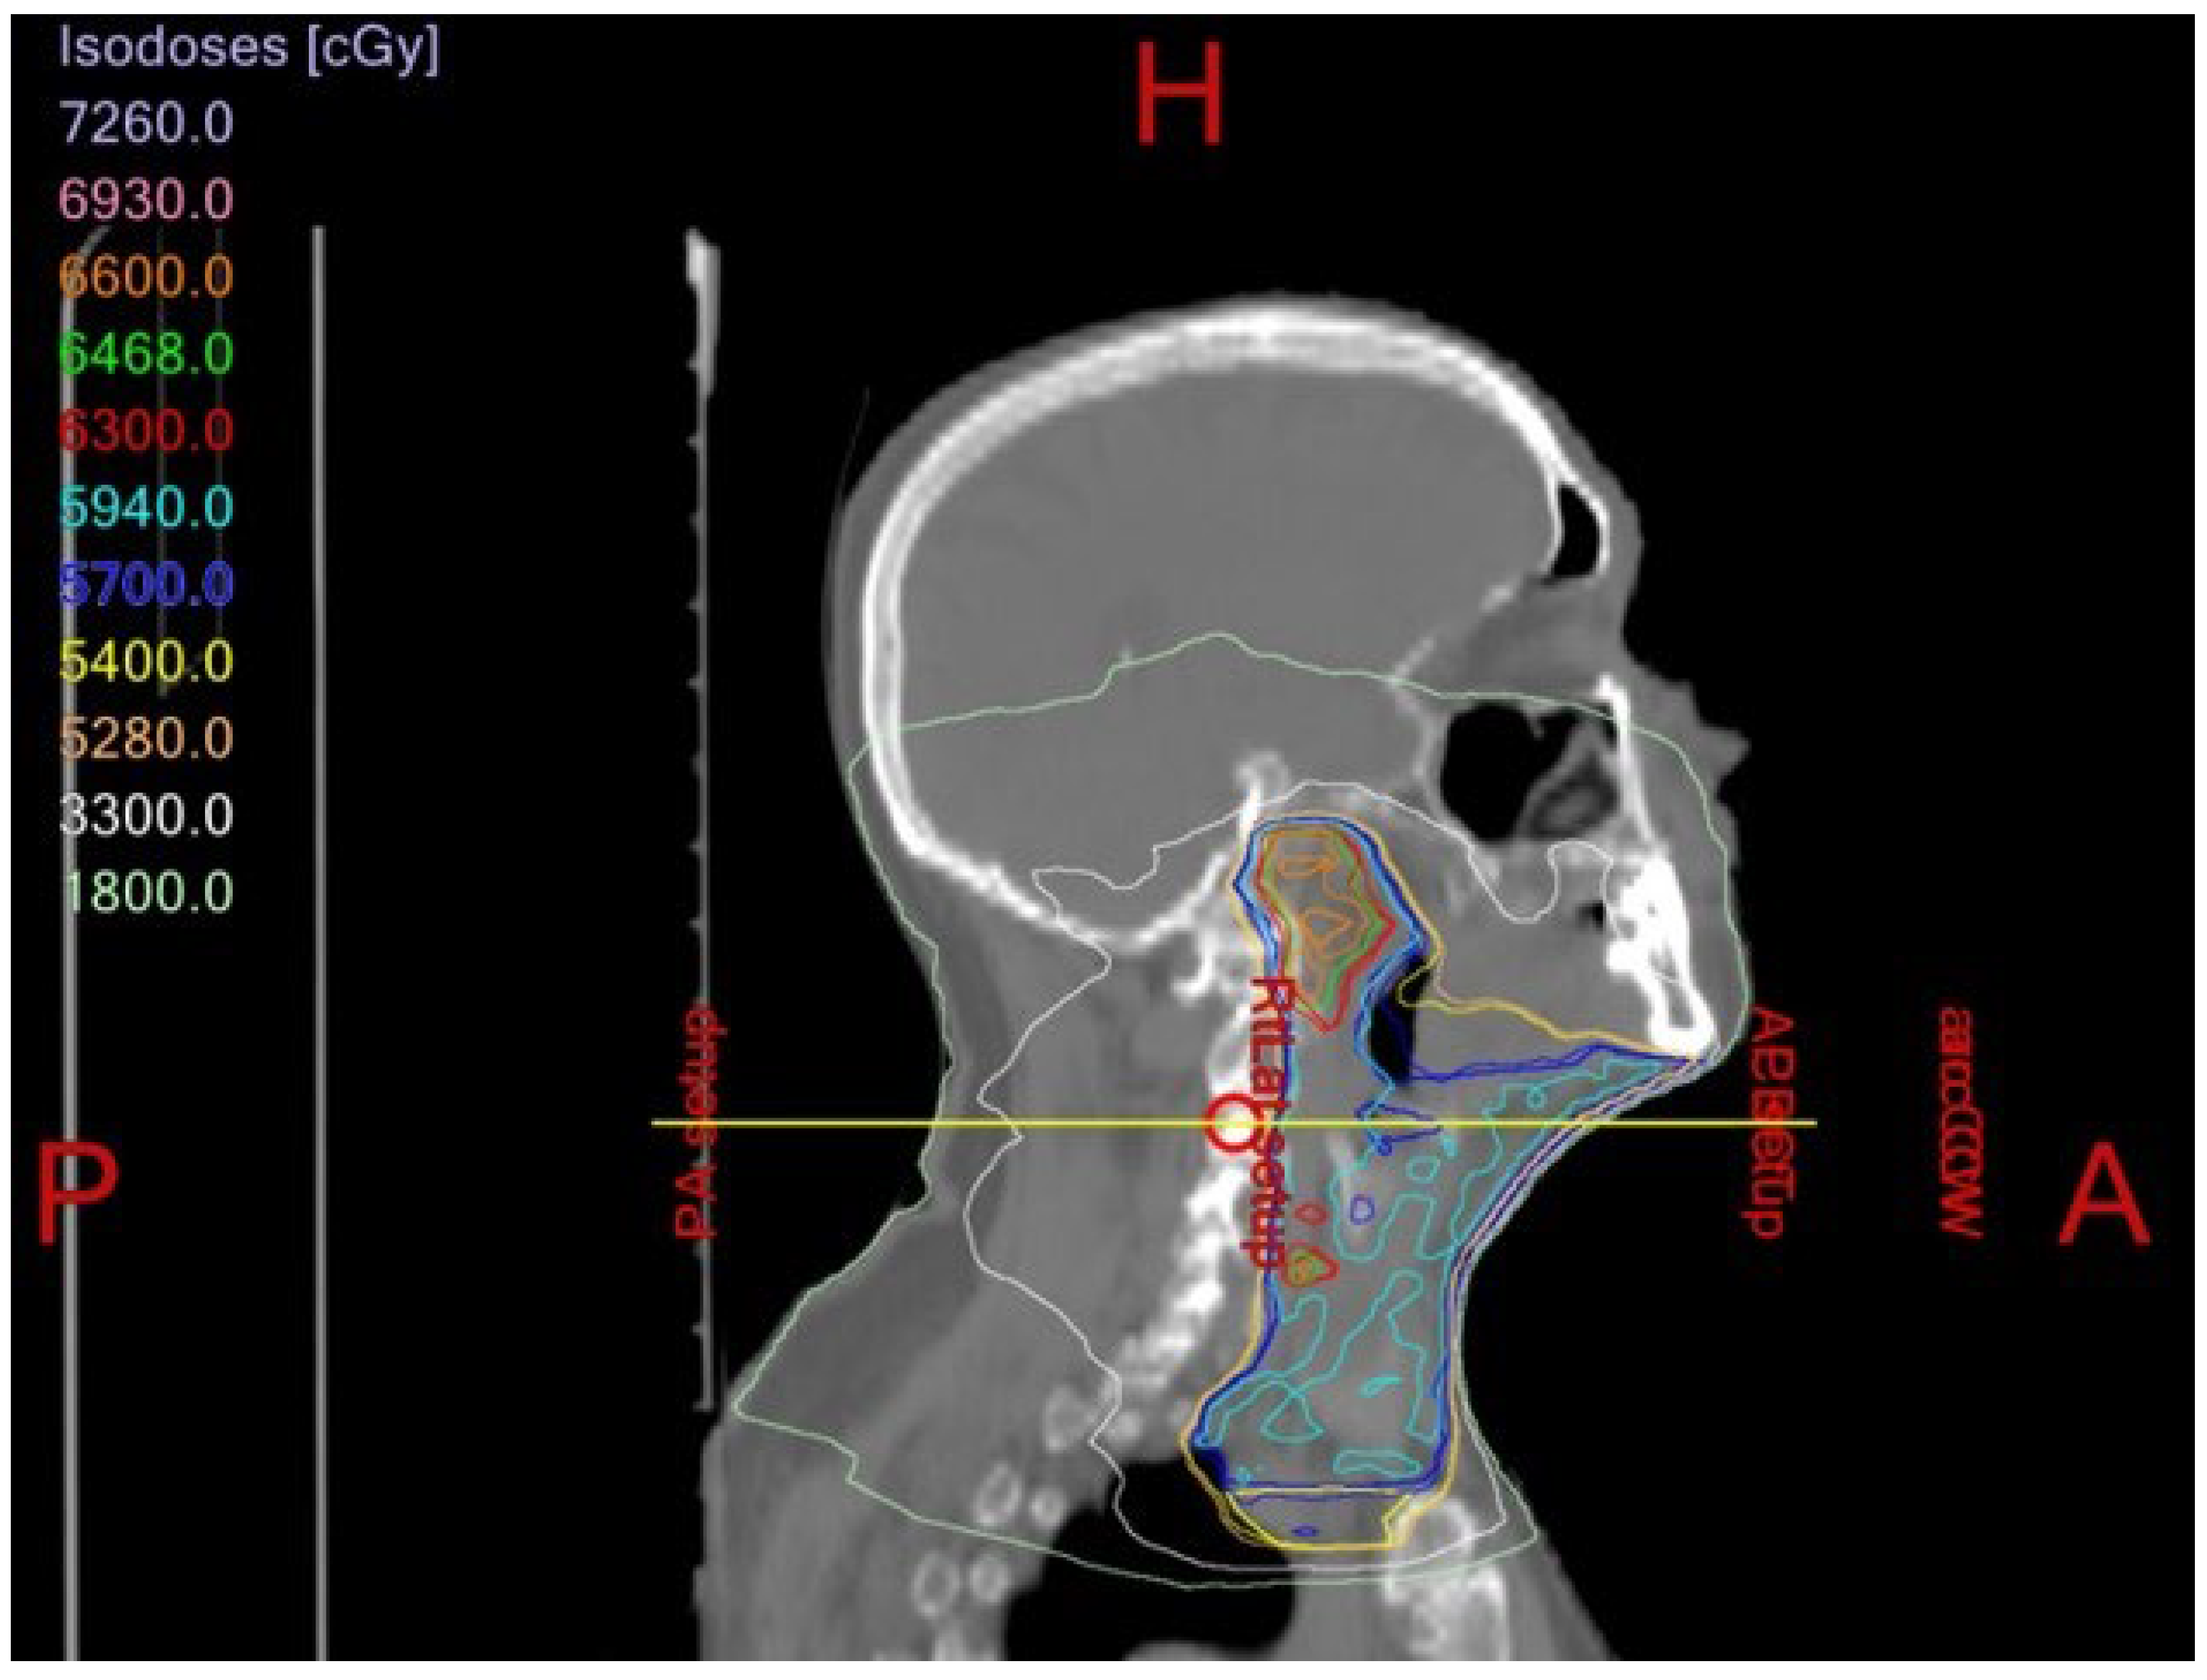

1.4. Osteoradionecrosis

Prevention and Management of Osteoradionecrosis